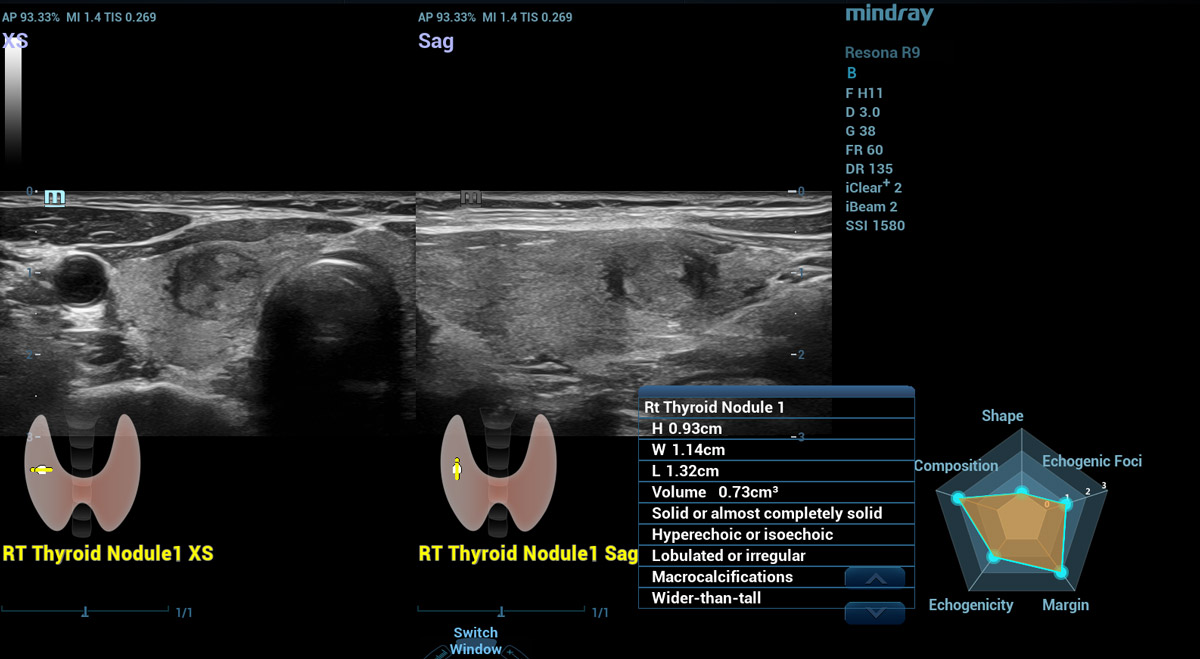

Smart Thyroid

O Smart Thyroid ûˋ uma ferramenta de anûÀlise e relatû°rio da tireoide para tornar a rotina clûÙnica de exames de tireoide mais precisa e produtiva.

Nû°dulo no Smart Thyroid